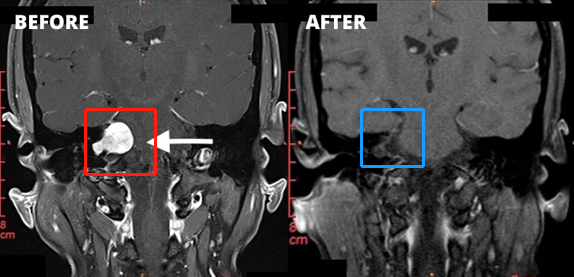

1、左侧图示(红色)患者术前核磁:右侧桥脑小脑角区见一类圆形占位性病变,边界清楚, T2WI高信号,其内信号欠均匀,增强扫描后病变呈明显强化,同侧桥脑小脑角池扩大,内听道扩大,四脑室轻微受压。

2、右侧图示(蓝色)患者术后核磁:术后肿瘤切除干净,做到了全切全切,核磁未见占位性病变。与术前对比明显可见肿瘤完整切除,较大限度减少复发可能。

3、患者术前情况:右耳耳鸣3个多月,听力下降,头昏头痛加重。面肌抽搐、舌头、牙龈和脸有麻木感觉,无法正常生活。

4、患者术后情况:术后1周出院,术后2周面神经功能House-Brackman分级1级。面神经保留,没有面瘫,听力保留。术后9个月随访,恢复很好,能够正常生活。

5、手术总结:听神经瘤切除手术规模较大的挑战是确定90%以上切除率的同时,既不损伤听神经、听力,也不损伤面神经,不会发生面瘫。以上肿瘤全切术由巴特朗菲教授操作,术后听力保留较好,且无面瘫。这样的手术效果堪称,这样的技术手法和水平即使是国际神经外科医院案例中也可以作为教科书级别的案例。